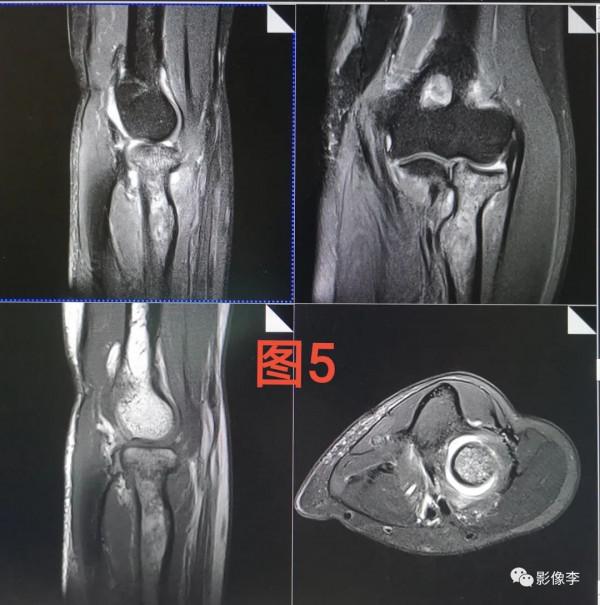

案例:見下圖圖3,患者穿著毛衣,做肘關節,發現定位像有偽影,考慮毛衣帶靜電,與線圈接觸出現放電現象,導致電磁干擾。然後讓患者蔣毛衣脫掉偽影消失,見圖4和圖5。出現這種現象的原因,暫時考慮是秋冬季節患者穿的衣服比較多,因磁共振檢查必須去除金屬異物,所以患者在進機房之前脫掉外層衣物時,衣物與衣物之間存在摩擦分離,導致衣物上存在靜電。但是為何靜電會出現在這種穿著毛衣的人身上了?其實靜電時時刻刻都存在著,只是看放電及不及時,電荷之間的中和快不快,由於秋冬季節天天氣乾燥,加上化纖面料類毛衣產生的靜電聚焦比較大(電壓比較大),很難發生中和,所以當這種靜電壓接觸到其它物質時導致放電,出現電磁輻射干擾。